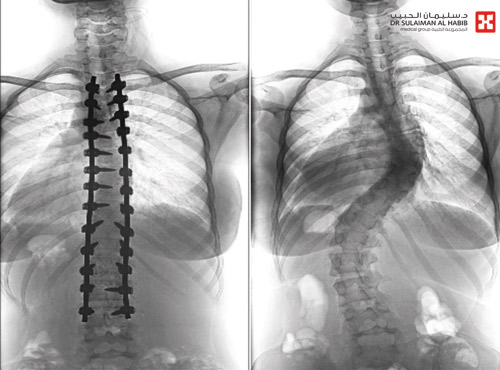

أجرى مستشفى الدكتور سليمان الحبيب بالفيحاء في جدة بنجاح عملية جراحية معقدة، لتقويم انحراف مزدوج ومتزايد بالعمود الفقري «جنف»، بدرجة «63» و«45»، وتثبيت ودمج الفقرات، لفتاة عمرها «17» عاماً، وأنهت العملية التي استمرت «6» ساعات، معاناة الفتاة مع أعراض حادة لازمتها لفترة طويلة، ذكر ذلك د. صلاح الدين خليفة استشاري جراحة العظام والعمود الفقري.

وقد راجعت الفتاة المستشفى وهي تشتكي من تحدب وإنحاء جانبي، قيد حركتها وغير نمط حياتها، وعقب وصولها تم إخضاعها للفحوصات والأشعة اللازمة حيث أكدت النتائج وجود انحراف مزدوج بزاوية «63»، و «45» درجة. وقد أجريت لها عملية جراحية، تم فيها تقويم العمود الفقري باستخدام البراغي والقضبان المعدنية، وتثبيت ودمج الفقرات، واستخدمت في العملية مجموعة من أحدث الأجهزة منها الجراحة الملاحية والميكروسكوب ومراقبة الأعصاب التي ساهمت في نجاح العملية.

وقد أكدت فحوصات ما بعد العملية تعديل المَيْل مع الحفاظ على سلامة الأعصاب، إضافة إلى أن الفتاة استعادت القدرة على الحركة والمشي بتوازن، والاستلقاء والنوم على ظهرها، فضلاً عن القوام والمظهر الطبيعي، بعد تعديل وضعية الحوض والكتف، كما أن طولها مع النجاح الكبير للتعديل زاد «5» سم.